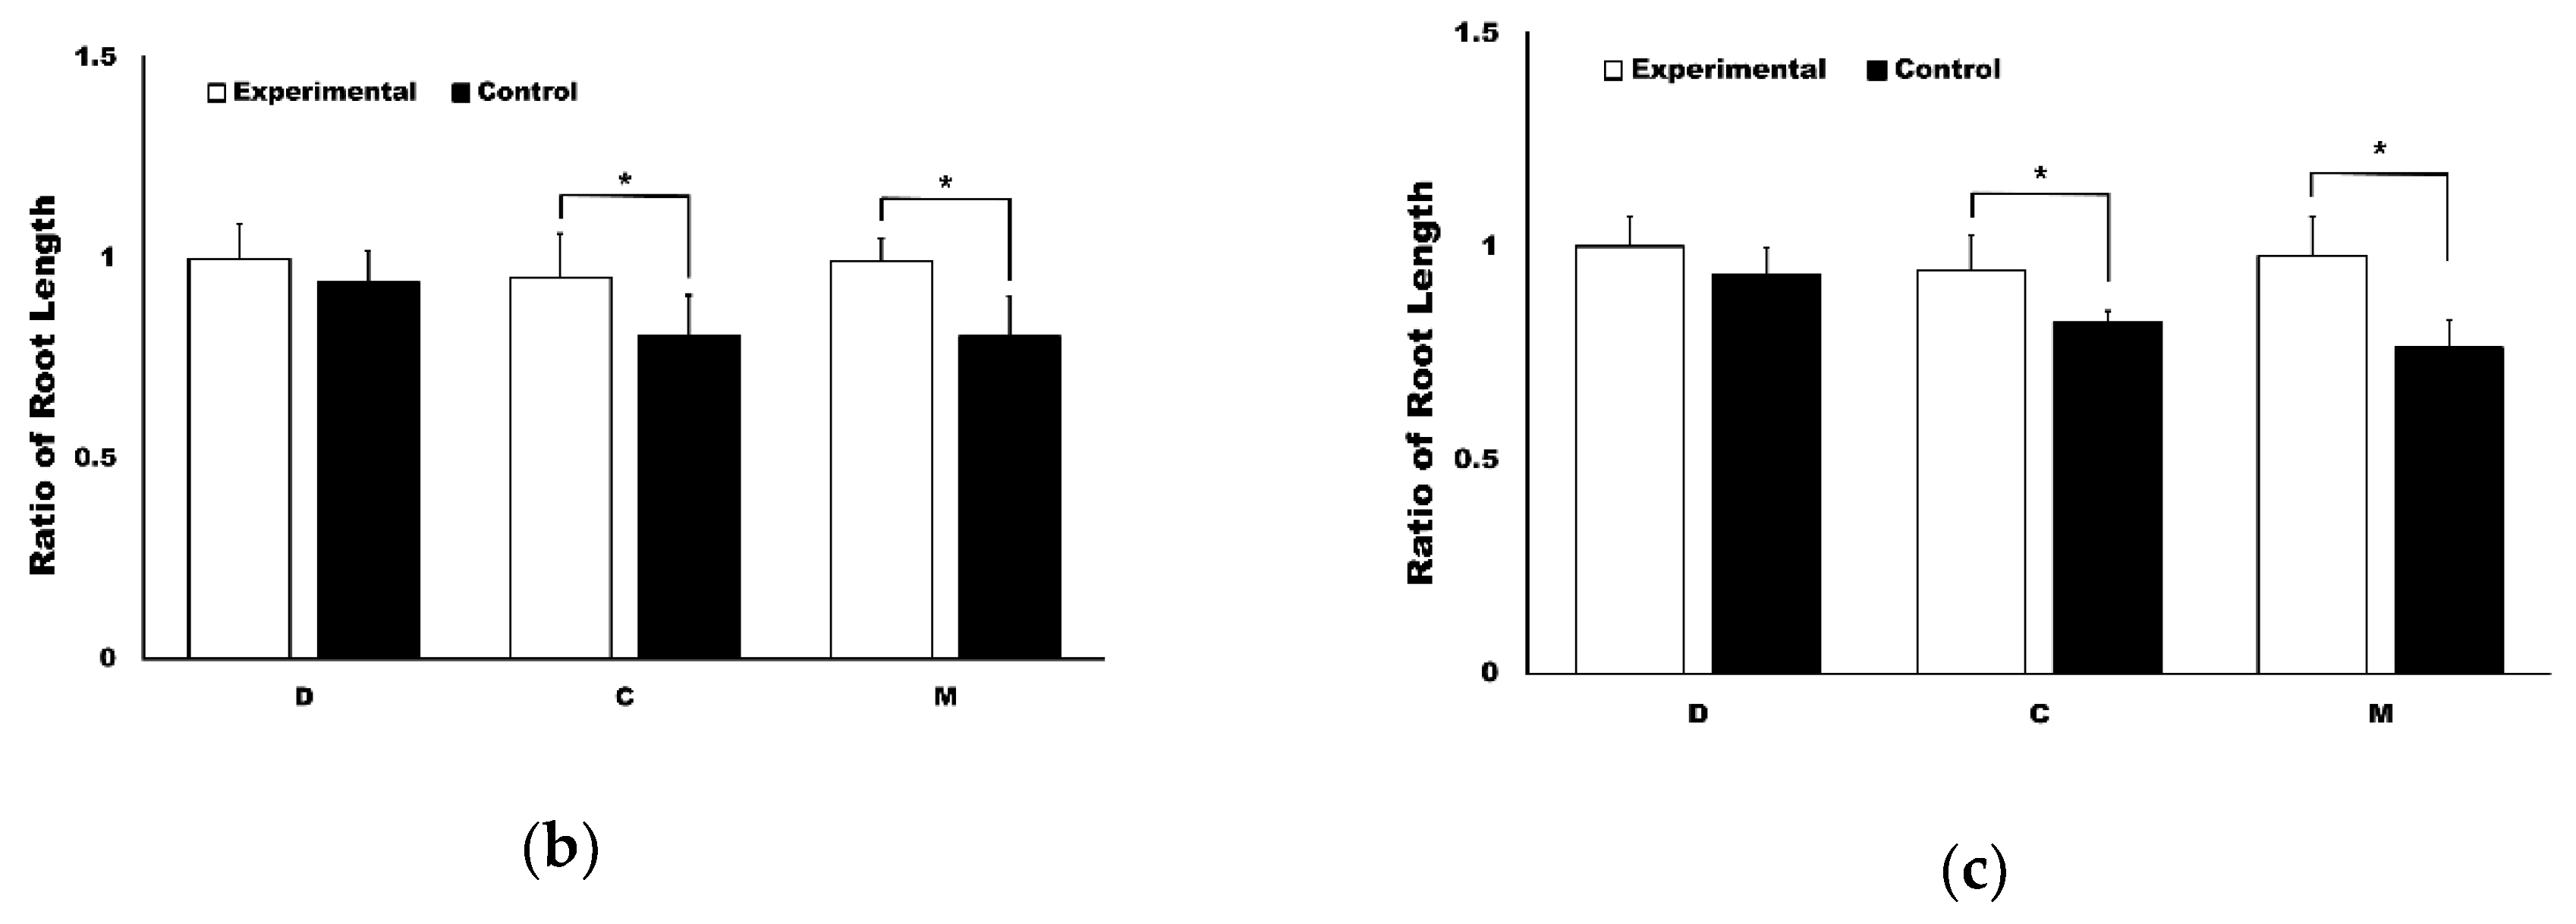

3.1. The Application of 4HR Inhibited Root Resorption during OTM

| Group | Male | Female |

|---|---|---|

| Control group | 69.25 ± 1.51% | 68.68 ± 0.79% |

| Experimental group | 71.69 ± 0.88% * | 71.52 ± 1.85% * |